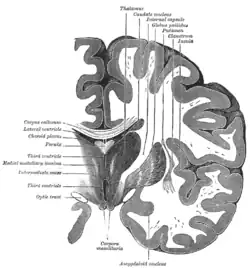

![]() Coronal section of brain through intermediate mass of third ventricle. (Putamen labeled at top.) | |